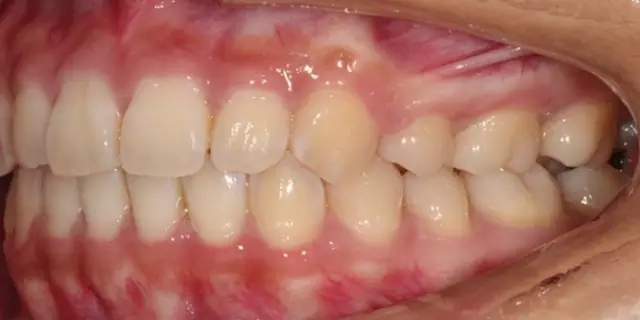

Damon 病例分享:安氏 II 類二分類露齦笑的矯治(董一磊)

治療前后對比